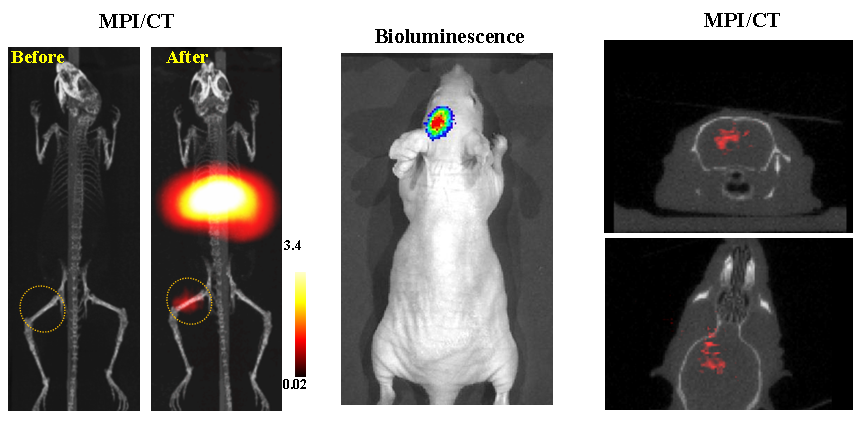

今年二月份,宋国胜教授与斯坦福大学饶江宏教授合作,通过系统的研究获得了影响磁性粒子成像信号的作用规律和关键原理,开发了新型磁性粒子探针---FeCo合金粒子,并首次应用于磁性粒子成像(MPI)。该造影剂在极低含量时(5 ng)仍具有很强的造影效果。这意味着,未来在进行人体成像时,可以使用更小剂量的造影剂,从而避免高剂量造影剂引起的肾肝损伤。基于MPI的直接成像原理,我们可以对造影剂进行正相和无背景干扰的活体成像,极大地提高信噪比。这项技术为肿瘤早期诊断、癌细胞示踪、脑中风、药物输送治疗、肺部灌注成像、胃肠出血、神经退行性疾病、磁热治疗等在活体中的可视化研究,提供了强有力的手段。相关研究成果以opta足球数据中文版为第一单位发表在Nature 子刊《Nature Biomedical Engineering》。该期刊是“生物医学工程”的顶级期刊。宋国胜教授为该论文的共同通讯作者。